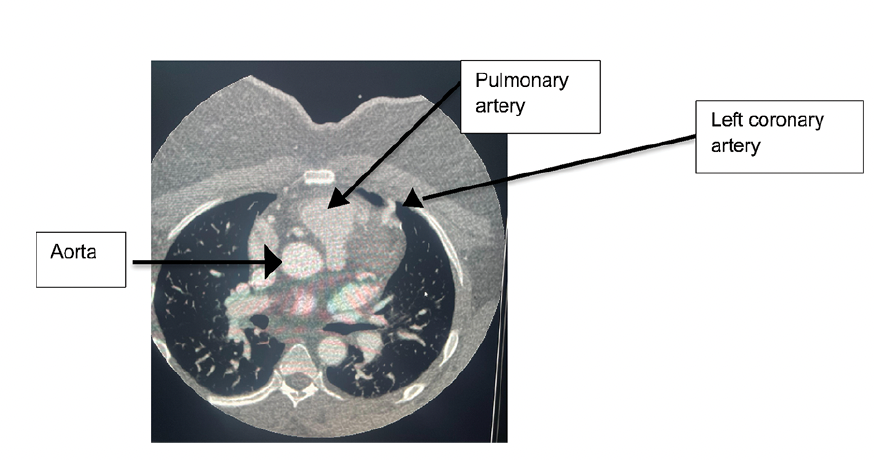

Subsequently, the patient underwent coronary CTA (CCTA) that confirmed the diagnosis (Figure 3) and showed the anomalous left coronary artery originating from the right margin of the main pulmonary artery just proximal to the main pulmonary artery bifurcation (Figure 4).